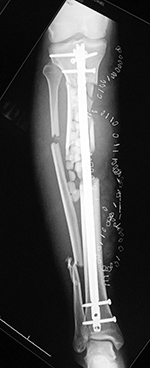

43 year-old man with comminuted right tibia and fibula fractures as well as extensive bone loss and soft tissue injury. A tibial intramedullary nail with proximal and distal locking screws is present as well as multiple rounded bony allografts. There are also large skin staples.